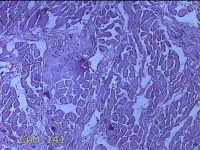

性别

男

年龄

26岁

临床诊断

皮脂腺囊肿

一般病史

发现前额部结节3年余。

标本名称

前额部结节

大体所见

灰白暗红色结节0.8x0.7x0.2cm一个,表面糜烂。

图3